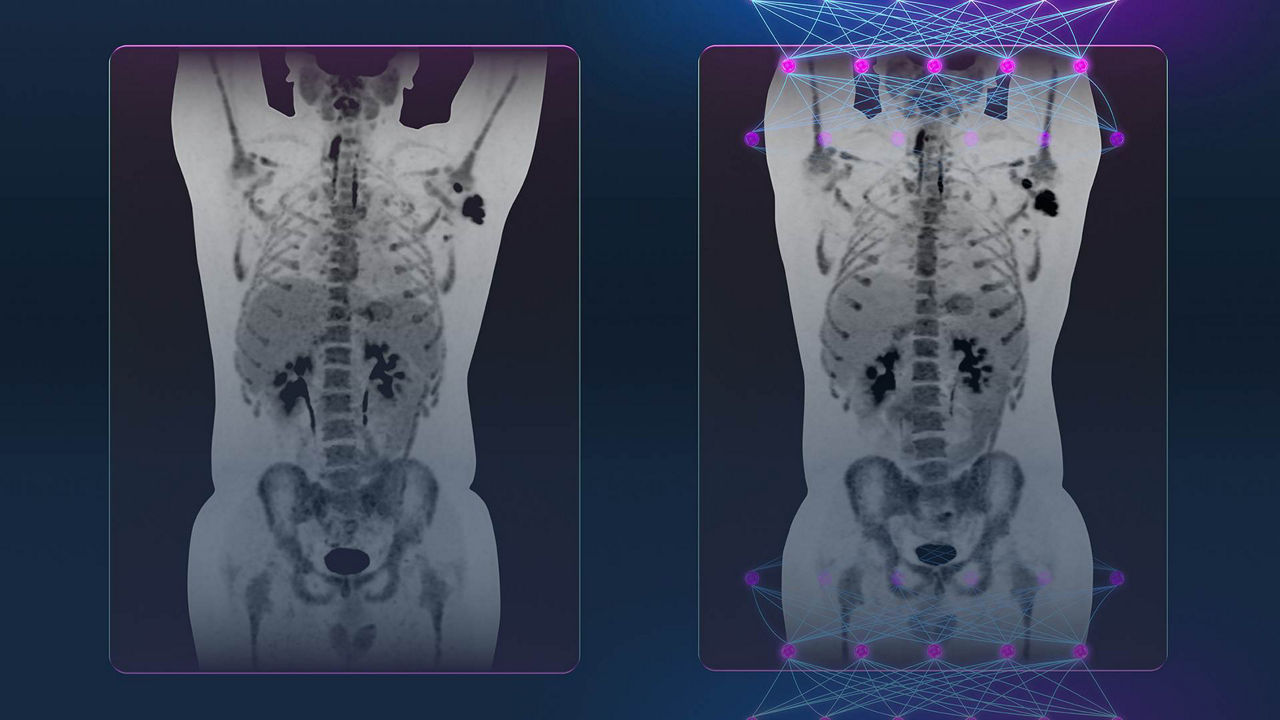

Leveraging transformational imaging technology to realize the promise of precision medicine and help deliver better outcomes. Our medical imaging products range from systems, including MRI, CT, PET, SPECT, Ultrasound, Mammography and X-ray, to digital and AI solutions to help drive healthcare digitialization, help enable faster exam workflow, improve clinical outcomes and increase efficiencies.